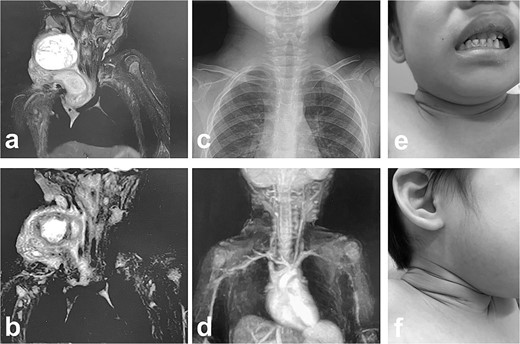

A male infant weighing 2726 g was born at 38 weeks of gestation. Antepartum ultrasonography and magnetic resonance imaging (MRI) revealed a right cervical cyst, suggestive of a lymphangioma. A right cervical cyst was noted at birth and gradually decreased in size thereafter. However, right cervical swelling became evident when he cried (Fig. 1a and b). An MRI obtained at 21 months of age showed a huge cyst in the right cervical mediastinal region. Following diagnosis of a lymphangioma with hemorrhage, he was treated with Eppikajutsuto®, a Japanese traditional Kampo medication, 2 g/d (0.2 g/kg). An MRI revealed tumor enlargement after oral administration of Eppikajutsuto® for 2 months. A complex vascular malformation was noted (Fig. 2) and the dose was increased to 5 g/day (0.5 g/kg). A repeat MRI 2 months after the dose increase showed no reduction in the size of the tumor. After another 4 months, the dose of Eppikajutsuto® was further increased to 7.5 g/d (0.65 g/kg). The tumor in the cervical region had enlarged further with an accompanying risk of airway system compression (Fig. 3a–c). A puncture and suction of the lymphangioma was performed for volume reduction and the content was prepared for bacterial culture. The content was dark red in color, which was consistent with hemorrhage. The white blood cell count (WBC) was 19 190/μl and the C-reactive protein (CRP) concentration was 5.77 mg/dl. He was admitted to the hospital to undergo treatment with intravenous and oral antibiotics. The bacterial culture results were negative. On the 22nd day of hospitalization, the WBC count was 8780/μl and the CRP concentration was 0.39 mg/dl. On the 24th day of hospitalization, a Denver shunt was inserted from the right cervical region to the abdominal cavity to reduce the volume of the cervical cyst to prevent airway obstruction (Fig. 4a–c). A pump chamber with a backflow prevention valve was implanted in the right anterior chest subcutaneous tissue (Fig. 4b). By applying pressure to the chamber, the cyst fluid in the neck was returned to the abdominal cavity. The patient was discharged on the 6th post-operative day. The swelling in the right neck was reduced and the pressure on the trachea was relieved based on the X-ray findings (Fig. 4c and d). On the 5th day after hospital discharge, the patient was febrile and the right neck swelling recurred. A hemogram revealed severe anemia and bleeding within the neck cyst was suspected. He was readmitted to the hospital and on the 2nd day after admission the cervical cyst was punctured, which yielded bloody contents. A transfusion was performed for anemia secondary to hemorrhage in the neck cyst. Sirolimus (1 mg), a mammalian target of rapamycin inhibitor, was added 7 months after starting Eppikajutsuto® due to a concern that administration of a Kampo medication and insertion of the Denver shunt might not be effective. An X-ray showed that the tip of the catheter may have moved within the cyst, which caused the catheter tip to penetrate the cyst and resulted in bleeding within the neck cyst (Fig. 5a). Serial MRI findings showed that the old bleeding site was within the mediastinal region of the lymphangioma. Revision surgery was performed 3 weeks after inserting the Denver shunt. Intraoperative findings showed that the tip of the catheter had penetrated the cyst wall (Fig. 5c). There were cyst walls with a septum on the mediastinal side of the cyst and when incised old bleeding was noted and the walls were opened as much as possible (Fig. 5d). The tip of the catheter was rounded and fixed with threads. The catheter was returned to the cyst and the wound was closed (Fig. 5b). The patient was discharged 9 days after the 2nd surgery. The concentration of sirolimus on the 14th day of administration was 9.9 ng/mL (normal range: 5–15 ng/ml). On the 16th day after the second hospital discharge, the neck had enlarged, the surgical wound was erythematous, and discharge was noted at the site of the pump chamber. Bacterial cultures of the punctured the neck cyst content and the wound discharge grew Staphylococcus aureus. On the 24th day after the 2nd hospital discharge, the blood concentration of sirolimus 1 month after starting oral administration was 19.7 ng/ml. Therefore, the oral administration of sirolimus was temporarily discontinued. At the same time the patient developed a high fever and the 3rd operation was performed to remove the Denver shunt due to a catheter infection. The blood concentration of sirolimus 6 days after discontinuation was 1.4 ng/ml. An MRI on the 6th post-operative day from the 3rd operation revealed two different intensities in the neck and mediastinal regions where the Denver shunt was inserted (Fig. 6a). On the 10th day after the 3rd operation, the patient was discharged from the hospital but laboratory testing showed an elevated WBC count (13 250/μl) and CRP concentration (6.03 mg/dl). Three months after the 3rd hospital discharge, the right neck swelling abruptly decreased in size and the WBC count and the CRP concentration decreased to the normal range. An MRI 2 months after the 3rd operation showed that the mediastinal lesion was smaller with near-complete regression (Fig. 6b). The neck swelling was minimal 6 months after the 3rd operation. An X-ray showed no tumor shadow and no compression of the trachea by the lymphangioma (Fig. 6c) and magnetic resonance angiography (MRA) showed that the lymphangioma had regressed (Fig. 6d). Currently, no right cervical swelling is evident when the patient cries (Fig. 6e and f) and he is doing well with oral administration of Eppikajutsuto® (7.5 g/d [0.65 g/kg]).

MRI findings after removal of the Denver shunt catheter. (a) MRI findings showed two different areas of intensity in the neck region and the mediastinal region where the Denver shunt was inserted. (b) MRI findings 2 months postoperatively showed that the mediastinal lesion was smaller with near-complete regression. (c) X-ray showed no tumor shadow and no compression of the trachea by the lymphangioma. (d) MRA showed disappearance of the lymphangioma. (e) and (f) Right cervical swelling did not become evident, even when crying (e: crying, f: smiling).